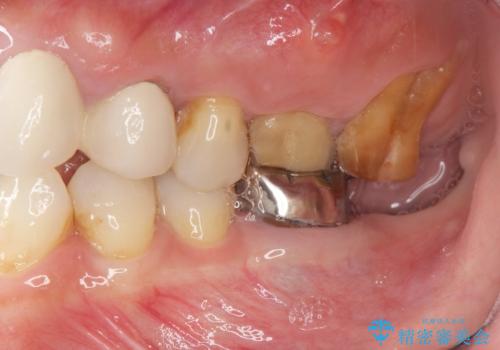

- 治療途中で前歯科医院に行かなくなってしまい、治療の続きを希望されて来院されました。

クラウンが装着されておらず、つぎはぎだらけの処置歯を、精度の高いセラミッククラウンを用いて歯ブラシのしやすい環境整備を行っていきます。